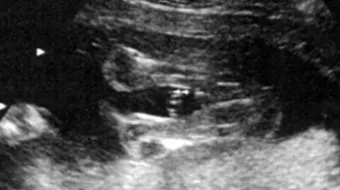

ويصبح غالباً بإمكان الطبيب معرفة جنس الجنين، وتحديد في الفترة ما بين الشهر الخامس والسادس؛ لأنّ أعضاءه التناسلية تكون واضحة جداً، وبذلك يتم التمييز بين الذكر والأنثى، علماً بأنها تبدأ بالتكوّن في الشهر الثالث؛ ولذلك يستطيع بعض الأطباء تحديد جنسه في الشهر الرابع.

طبيعة جهاز السونار

من أحدث الأجهزة المستخدمة للتعرف على جنس المولود، بالشكل التالي:

- يتم الاعتماد على موجات السونار، وتحديداً فوق السمعيّة لتقييم الحمل في المرحلة الأولى وبالأخص الثلث الأول خلاله، بحيث يتمكن الطبيب من تقييم حالة الجنين الصحية، والاطلاع على حالة الحمل ككل إن كان بداخل الرحم أو خارجه، وكذلك الكشف عن مشاكل في الرحم أو عنقه أو المشيمة التي يتغذى الطفل من خلالها، إضافةً إلى الكشف عن مشاكل أو عيوب في الجنين، وتحديداً الخَلقية منها.

- معرفة عمر الجنين وكذلك تفاصيله المتعلقة بالطول والنمو، ووضعيته وتقرير الطريقة الأنسب لولادته بناءً عليها.

- أمّا عن نسبة الخطأ المتعلقة بهذا الكشف فتبلغ تقريباً 40%، وهذه تكون في المرحلة الأولى من الحمل، أمّا في المراحل المتقدمة تقلّ إلى 20% و10%.